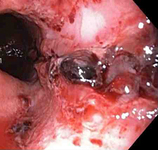

Mallory-Weiss tear

Mallory-Weiss tear after epinephrine injection (the bleeding has stopped, allowing better visualization of the lesion)

From the collection of Juan Carlos Munoz, MD, University of Florida